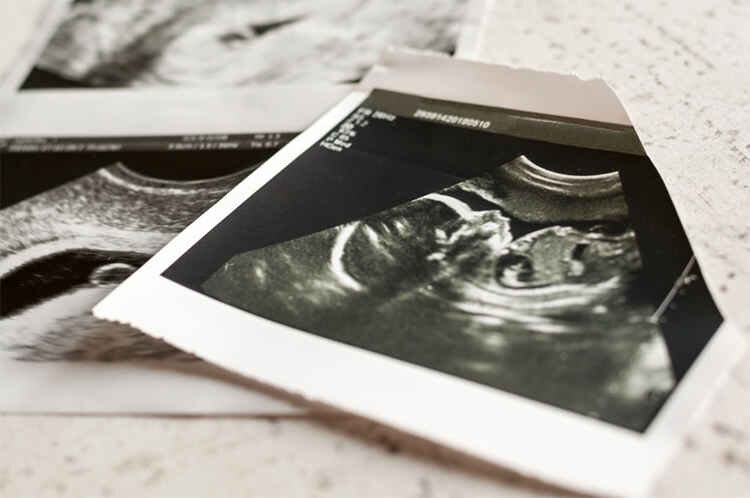

مبلغ نجومی سقط جنین غیرقانونی در ایران!

روزنو :طبق گفته یک ماما که سقط غیر قانونی انجام می‌دهد، اگر همه چیز نرمال باشد برای سقط جنین زیر سه ماه تقریبا ۷۰ میلیون و بالای ۴ ماه آن هم تنها یک هفته بیشتر از ۴ ماه با مبلغ ۱۵۰ میلیون کار را انجام می‌دهد.

یک پزشک عمومی در مورد هزینه این عمل‌ها می‌گوید که هزینه سقط جنین غیرقانونی تا ۴ ماه ۱۲۰ میلیون تومان است. البته افرادی هم هستند که چنین پولی ندارند، اما به این خاطر که ممکن است جانشان به خطر بیافتد با هزینه کمتر هم حاضر به انجام کار می‌شوم. اما اگر افرادی با تمکن مالی بالا برای این کار مراجعه کنند، بیش از ۱۲۰ میلیون از آنها می‌گیرم.